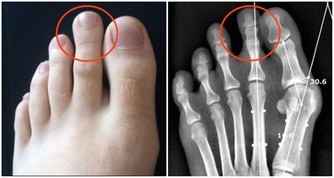

有文獻報導認為,癌細胞在增生分化過程中,會引起生長激素分泌異常。

大量的生長激素會刺激骨關節異常增生,侵犯膝、踝、腕等大關節,出現腫脹、疼痛等症狀。

據報導,老年人肺癌合併關節痛的發生率約佔10%至20%。

因此,對中、老年人突然逐漸加重的肩臂痛,無論是否伴有呼吸道症狀,

且肩臂痛經牽引或止痛藥治療,只能暫時緩解症狀而不能阻止疼痛進行性加重時,就需高度警惕。

應及時到醫院做檢查,以免誤診。